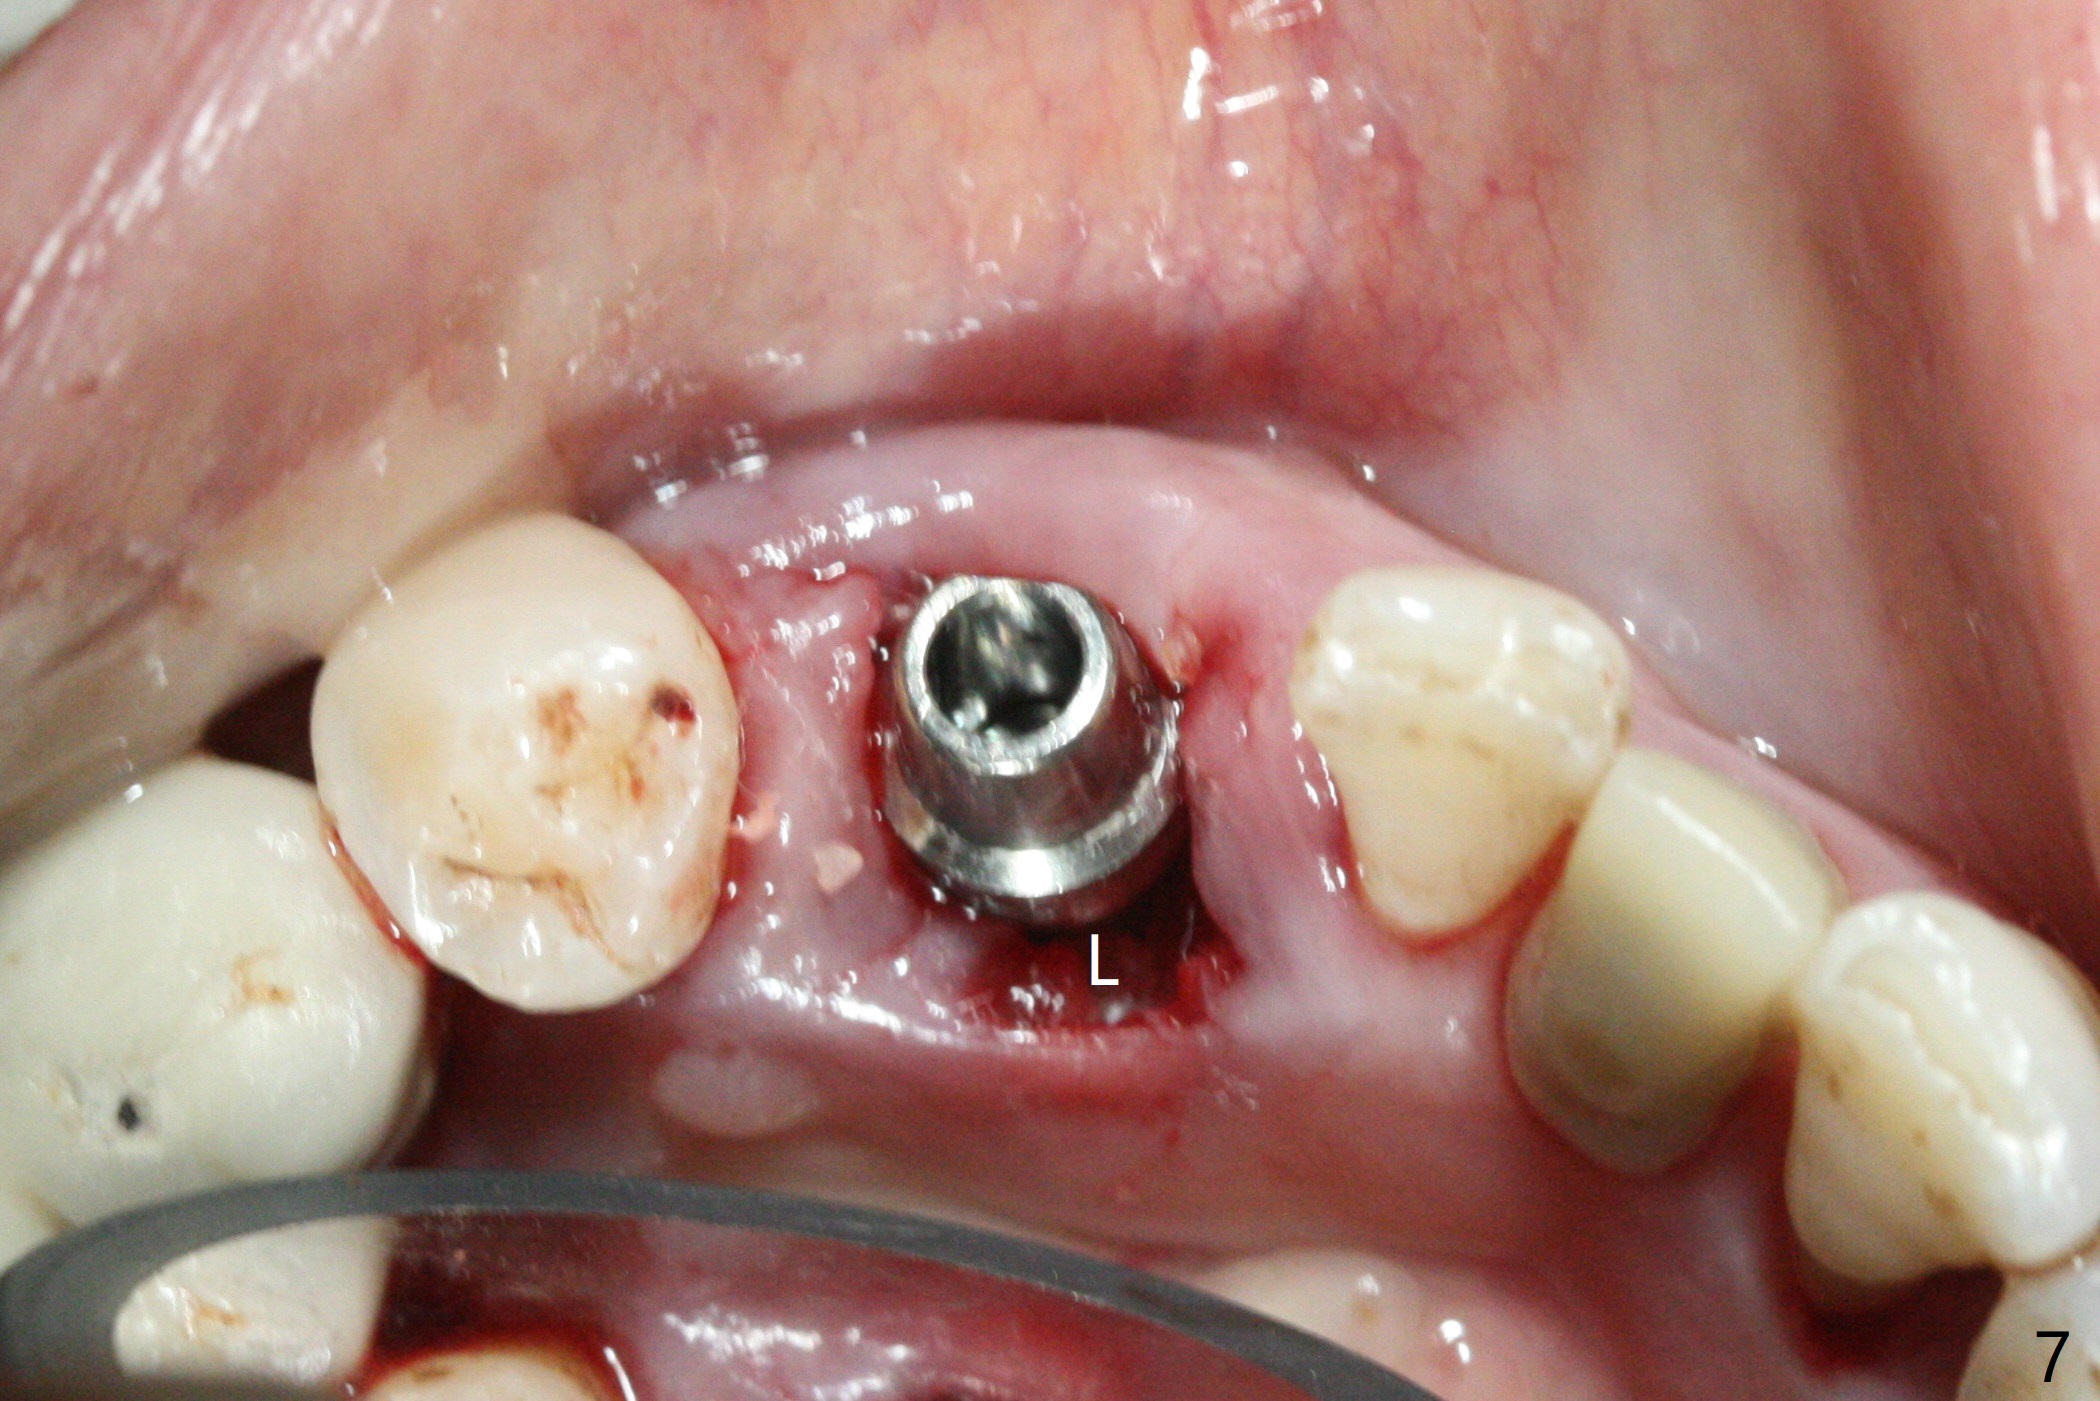

There is a fistula buccal to the apex of the tooth #23 preoperatively (Fig.1), which is related to loss of the buccal plate of the socket of #23. Therefore an implant is placed mainly in the socket of #22 (Fig.3). The lingual (Fig.2 L) gingiva appears to have more extensive inflammation. After extraction, the lingual (Fig.3 L) gingival margin is significantly lower than the buccal one. The lingual crest is ~ 4 mm lower than the buccal one. A 3.8x10 mm dummy implant is placed tentatively with an apical space (Fig.4). When a same dimension definitive implant is placed with 40 Ncm, it is 2 mm below the lingual gingival margin, whereas 6-7 mm below the buccal one (Fig.5). Vanilla graft is placed before placement of a 5.5x4(5) mm abutment (Fig.6,7). There is a 2-3 mm lingual (L) gap to be filled with the allograft secondarily to prevent periimplantitis (Fig.7). Later the abutment is changed to a longer and smaller one (Fig.8) with more of the allograft (*). After trimming of the abutment (Fig.9 (*: papilla between the fused teeth)), an immediate provisional is fabricated to close the socket (Fig.10, similar to Fig.1). The majority of the bone graft seems to be in place 8 months postop (Fig.12). The implant appears to have been placed buccal, consistent with the thin and slightly erythematous buccal gingiva (Fig.13). The ridge completely regenerates 2 years post cementation (Fig.14).